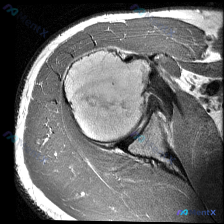

看到一个肩部病例,患者被怀疑有盂唇病变,但当前提供的T1加权轴位MRI显示盂唇形态完整、信号正常,无明显撕裂或异常。这个矛盾点比较值得讨论,大家怎么看? 先放影像分析结果的核心部分: - 骨骼结构:肱骨头形态圆滑,骨髓信号均匀中高,无骨折或骨质破坏;关节盂边缘清晰,骨质结构完整。 - 关节与盂唇:关...

整理了一份肩关节MRI的病例资料,初诊临床因为肩痛怀疑盂唇病变,先放出单层T2冠状位的核心影像表现(文字版): 1. 冈上肌腱止点处信号增高,无明确连续性中断 2. 肩峰下-三角肌下滑囊可见大量积液 3. 盂唇形态完整,未见明确撕裂征象 这个病例已经有完整的影像分析结论,暂时先不放。大家基于当前给出...